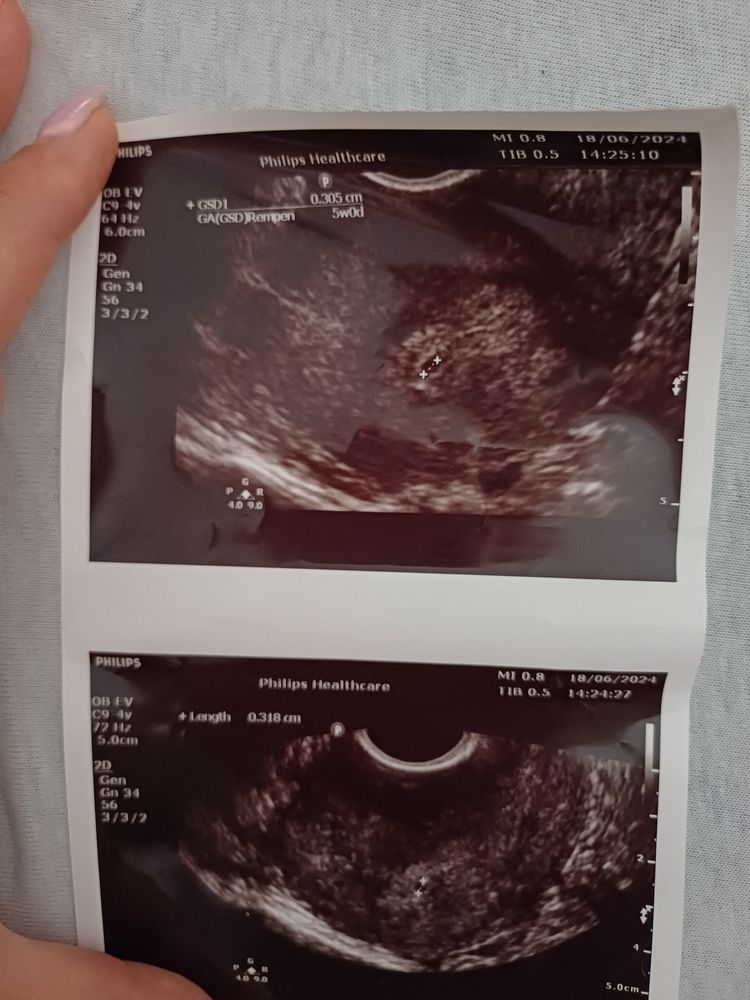

Поехала на узи , хотя мне было назначено на 20 июня. Доктор сказал что результат сомнительный , повторить через 2 дня. Что то похожее на ПЯ он видит но не точно. Прикладываю результат узи, девочки кто разбирается посмотрите пожалуйста есть ли надежда 🙏

P.S По ходу в лаборатории вышла ошибка, 20 Июня хгч вышел 4200 ! На узи ПЯ соответствует сроку 🧿❤️😘🙏 слава богу !! Растём дальше